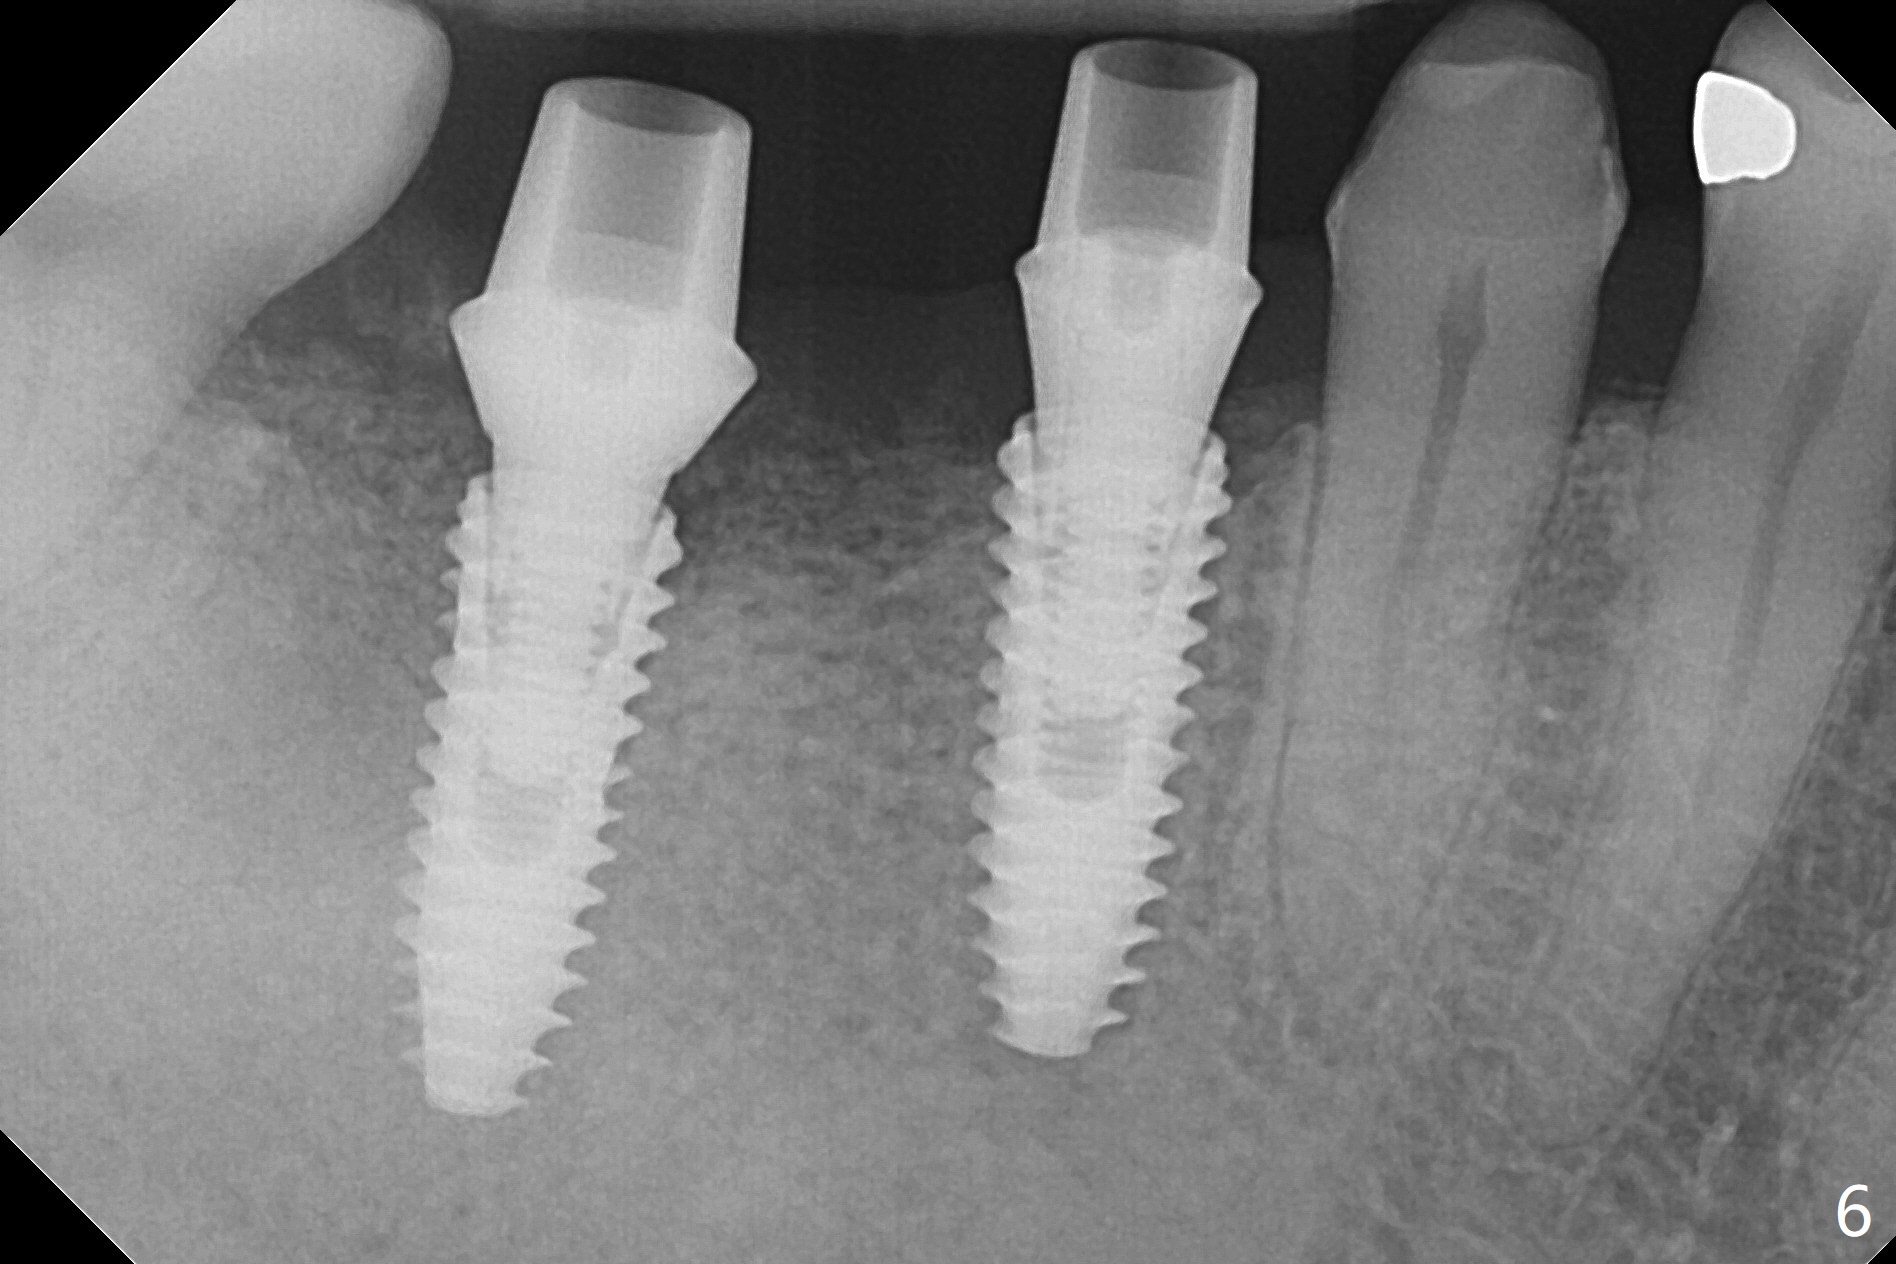

The edentulous area at #30 looks narrow after #31 extraction (Fig.1) and after incision (Fig.2). As planned, osteotomy is established at #30 as a premolar and at the mesial slope of #31 socket (Fig.3). Following adjustment of the trajectory at #30 and sequential osteotomy until 3.5x11.5 mm, two of 4x10 mm dummy implants are inserted with stability as well as dummy abutments (Fig.4). Final implants are 4x11.5 mm with insertion torque > 50 Ncm; after suturing, abutment margins are subgingival, particularly at #31 (Fig.5 (*: Vera Graft)). Periodontal dressing is applied. Provisional will be fabricated when the wound heals. It appears that the small and regular implants are appropriate for the narrow mesiodistal space at #30 and 31. There appears to be bone growth around the implants nearly 4 months postop (Fig.6).